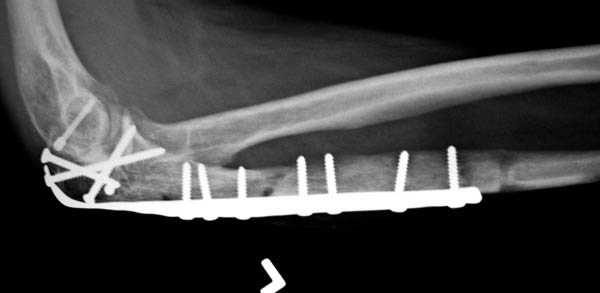

Для фиксации перелома локтевого отростка на сегодня множество преконтурных с блокирующими возможностями пластин.

Стабильную фиксацию, особенно при оскольчатых

переломах, можно добиться, применяя технику Bridge Plate, и за счет тех пластин, где имеется возможность проведения множественных шурупов (2.7 мм) проксимально.

Здесь выставлены несколько случаев и варианты фиксации локтевого отростка, некоторые в комбинации с другими переломами.

1 вариант применен ACUMED локинг пластина